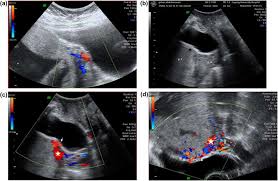

The diagnosis of Placenta Increta is usually made with ultrasound during antenatal screening , as in the case of the less severe accreta, there can be focal obliteration of the hypoechoic retroplacental zone detected on ultrasound.

N/B: When a placenta Increta occurs on the posterior or lateral walls of the uterus, it may be difficult to detect by ultrasound.

MRI is also valuable in the diagnosis of Placenta Increta if ultrasound is inconclusive.